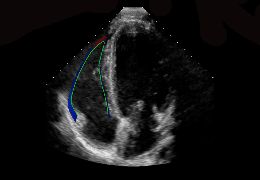

ART-Plan™ Artificial Intelligence Contouring